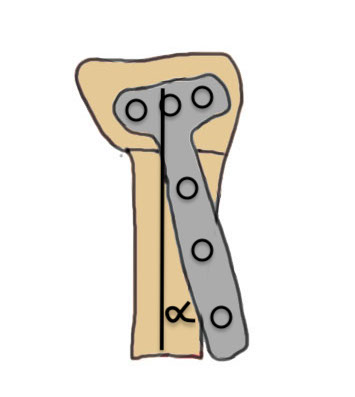

Volar versus dorsal radial osteotomy

- 28 patients undergoing osteotomy for radial malunion

- dorsal plate: increased complications including plate removal

- volar plate: increased undercorrection, difficulty with plate fitting

Dorsal opening wedge osteotomy

Advantage

Lengthens the distal radius

May be easier to correct in coronal and sagittal plane

Disadvantage

Dorsal approach / dorsal plate - extensor tendon issues

Technique

3 / 4 dorsal approach

- expose distal radius

- can use half pins to control distal fragment

- protect structures with homan retractors

- osteotomy with microsagittal saw

- correct radial articular surface in sagittal & coronal planes

- trapezoidal bi-cortical iliac crest autograft / synthetic graft

- dorsal locking plate